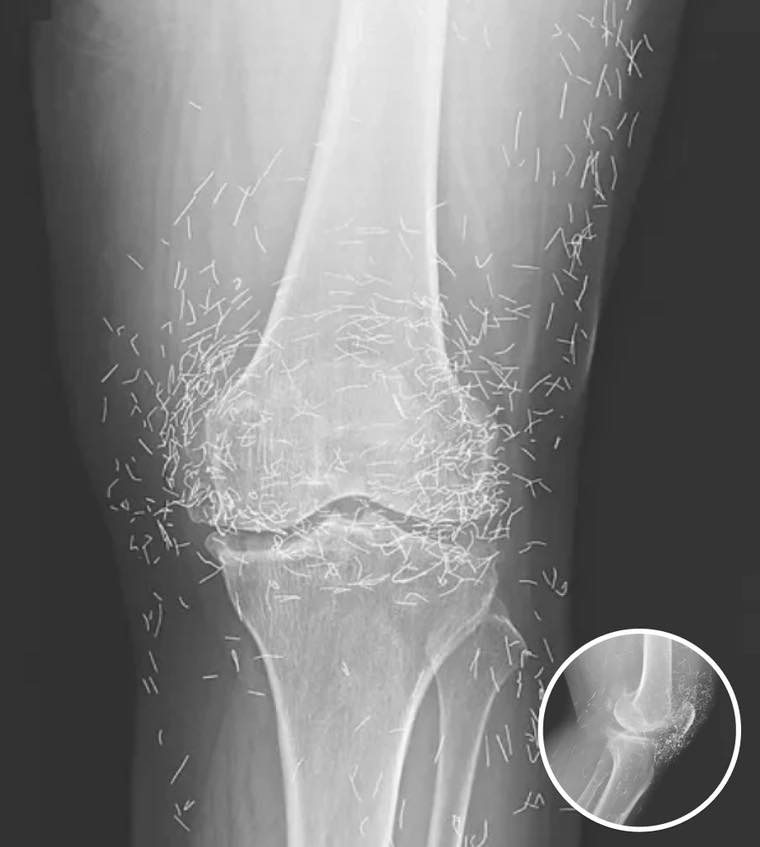

When Healing Turns Hazardous: The Woman with Gold Needles in Her Knees

When doctors examined a routine X-ray of a 65-year-old woman suffering from chronic joint pain, they expected the usual signs of osteoarthritis. Instead, they found something entirely unexpected: dozens of tiny gold needles embedded deep in her knee tissue. The woman had been undergoing acupuncture therapy for years. Initially, the treatments provided some relief, soothing…